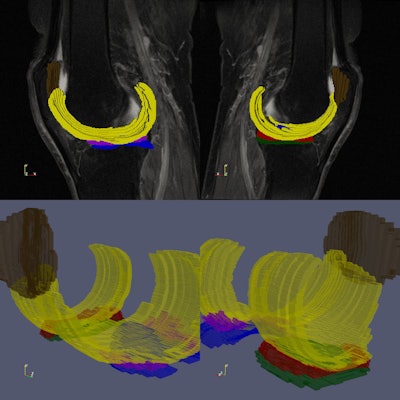

In the figure it is possible to see the images and ROIs used in this study: images were acquired using a sagittal intermediate-weighted turbo spin echo (TE = 30 ms, TR = 3,200 ms, FOV = 160 mm, Slice Thickness = 3 mm, In-plane Resolution = 0.36 mm × 0.51 mm, Bandwidth = 248 Hz/pixel, Matrix Size = 444 × 448 × 37). In yellow, the femoral cartilage, in brown, the patellar cartilage, in red, the medial meniscus, in green, the lateral TBL Cartilage, in blue, the medial TBL Cartilage, and in purple, the lateral meniscus. Image courtesy of Eros Montin, PhD.